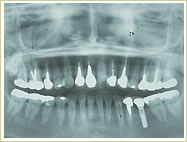

60歳 男性 インプラント埋入数:6本 画像拡大

治療前 治療後

治療前

治療後 治療後 治療後